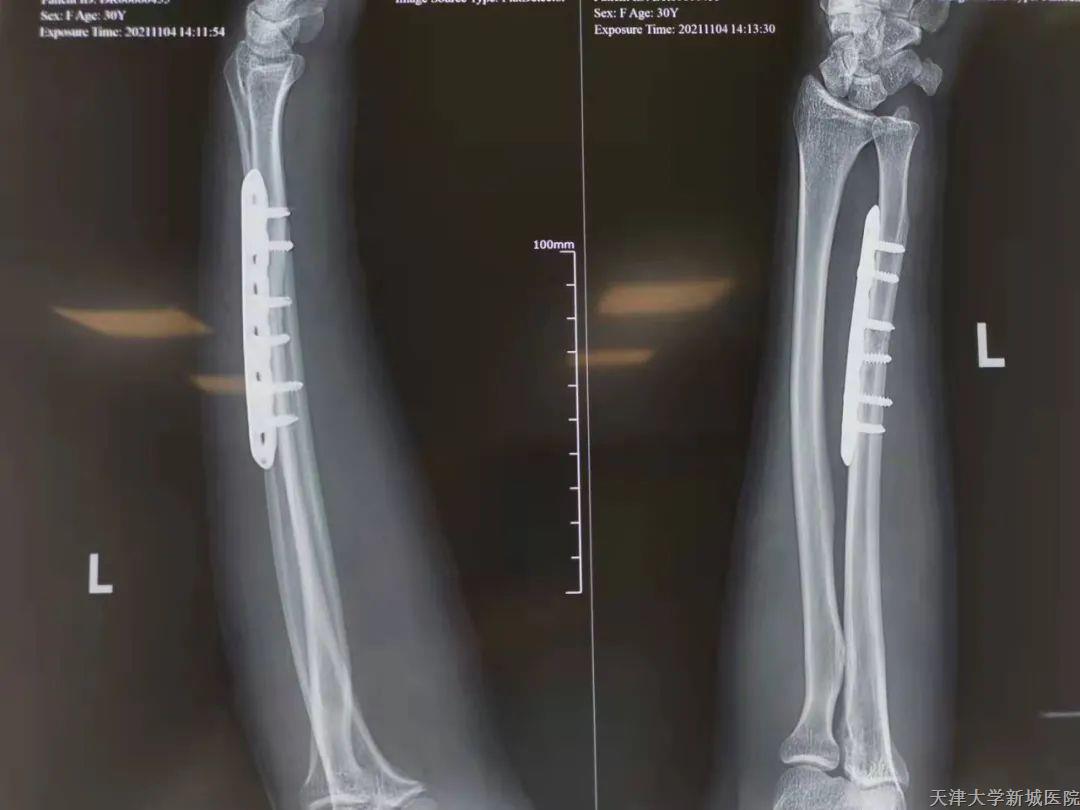

在杨平波主任主导下与刘元捷医生等医护人员在全麻下行左尺骨骨折切开复位内固定术,手术历时1个半小时,术后患者安返病房。患者后续恢复情况良好,住院期间也被医护人员耐心细致的服务所感动,因此才特意订制锦旗赠予综合外科全体医护人员。